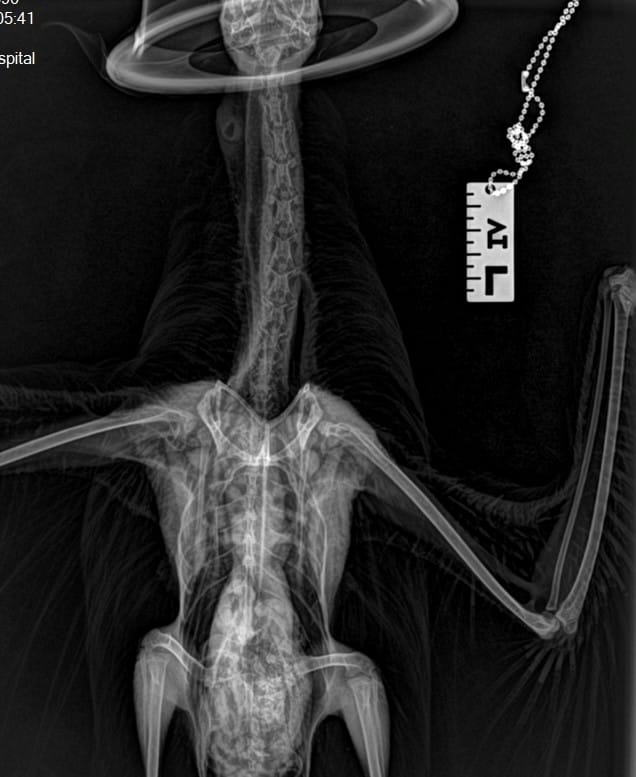

One such story was this Glaucous-winged Gull which had swallowed a skewer which presumably had chicken or some other meat on it, and in the process of trying to regurgitate it managed to drive the skewer though its throat!

The WRA team managed to successfully remove the skewer and rehab the gull. X-ray images below show the positioning of the skewer (even though the gull almost removed it on its own!). The following two images are the before and after radiographs. If you look closely enough you can see all the scar tissue it caused.